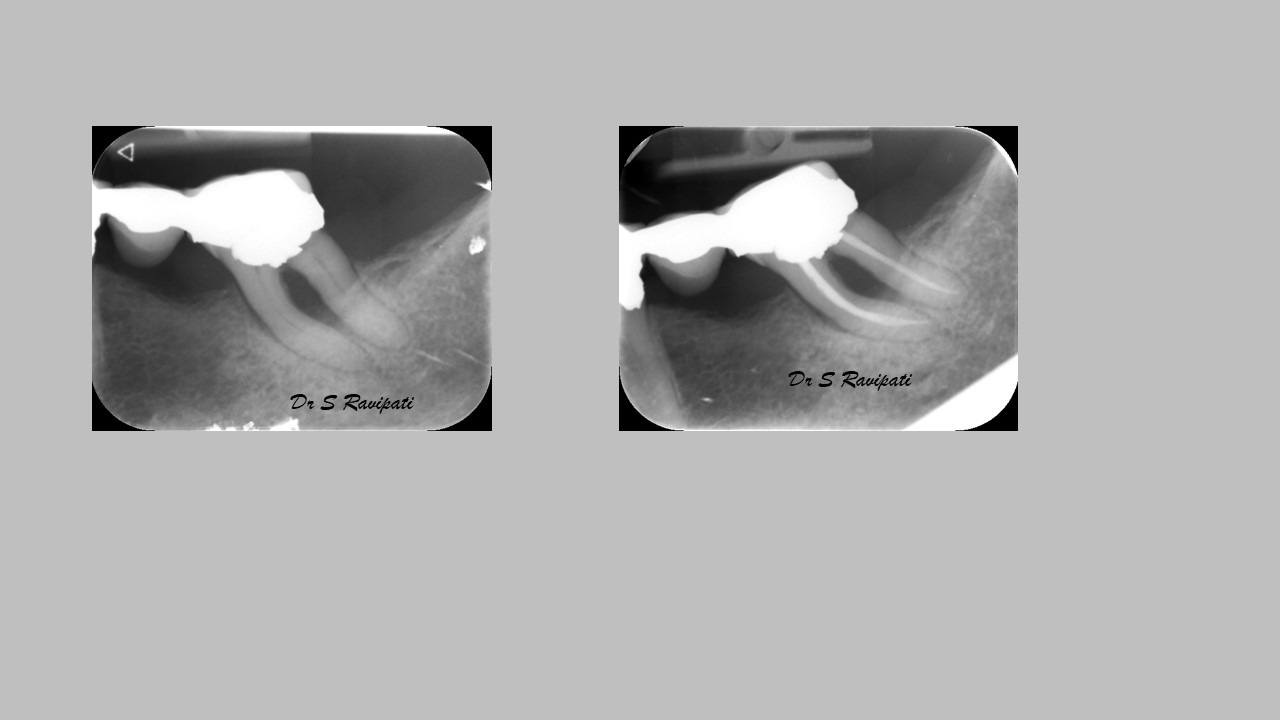

An access cavity is placed on the surface where the patient bites, to reach the root canals of the tooth. Once all the canals are identified, small files are used to remove the infected pulp.

Files of different sizes are used to eliminate bacteria and infection and to shape the canals. The canals are disinfected thoroughly with irrigants and later the canals will be sealed in 3 dimensions with a special medicament called gutta-percha to prevent reinfection of the tooth and the access cavity will be sealed with a temporary filling.